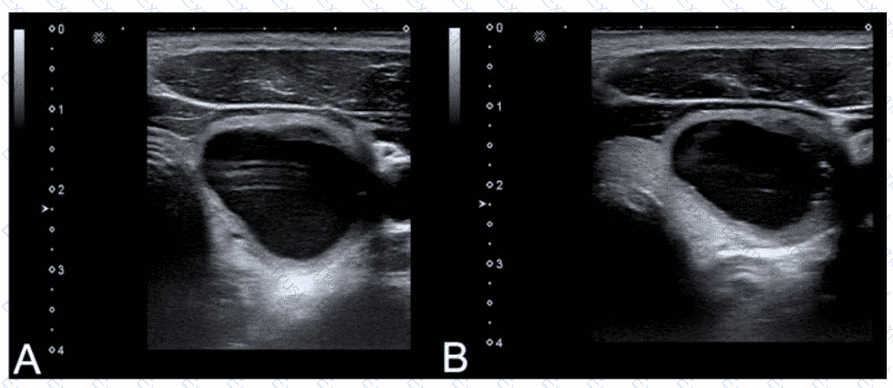

Which adjustment will reduce the artifact in the cystic lesion in image A resulting in image B?

Options:

A.

Turn off harmonics

B.

Increase dynamic range

C.

Turn on edge enhancement